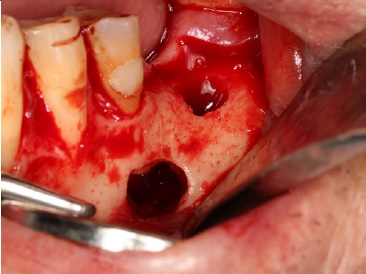

Exame extraoral mostrou ausência de sinais de alterações patológicas. Exame intraoral mostrou ausência do dente 36 e fístula na região de rebordo alveolar, com drenagem de secreção purulenta (Figura 1).

Figura 1 Aspeto clínico intraoral mostrando fístula na região de rebordo alveolar de área edêntula, correspondente ao dente 36.

Foi realizada incisão e descolamento do retalho mucoperiósteo por vestibular, na região dos dentes 34, 35 e 36, expondo o trajeto fistuloso. Após osteotomia, realizada com broca esférica n.º 6, para acesso ao ápice radicular (Figura 4) e apicectomia do dente 35, utilizando broca troncocónica n.º 701 para peça reta (Figura 5), foi realizada coleta de fragmentos da lesão cística (Figura 6) e armazenamento em solução de formol a 10%, para exame anatomopatológico. Em seguida foi realizada a sutura para cooptação das bordas do retalho e instalação de um dispositivo de acrílico, removível, confecionado no momento da cirurgia, na região da fístula localizada na região do dente 36 (Figuras 7 e 8).